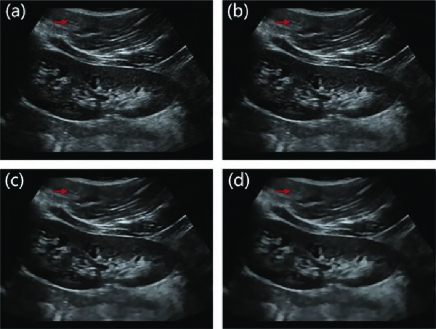

Fig. 6 and Fig. 7 depict the despeckled results of different filters in the first row and show the corresponding local zoomed-in results in the second row. Visually, our method achieves the best performances in feature preservation and noise removal. According to the streak shown by the red arrow in Fig. 6, the PFDTV method produces the clearest edges. NLLRF only preserves a part of the streak while SRAD reduces the contrast of the streak heavily. Other filters remove the streak after speckle reduction. Similarly, according to the nodules indicated by the red arrow in Fig. 7, the PFDTV method succeeds in enhancing the local contrast. SRAD, OBNLM and NLLRF reduce the contrast of the nodules heavily. Other filters remove the nodules after despeckling.